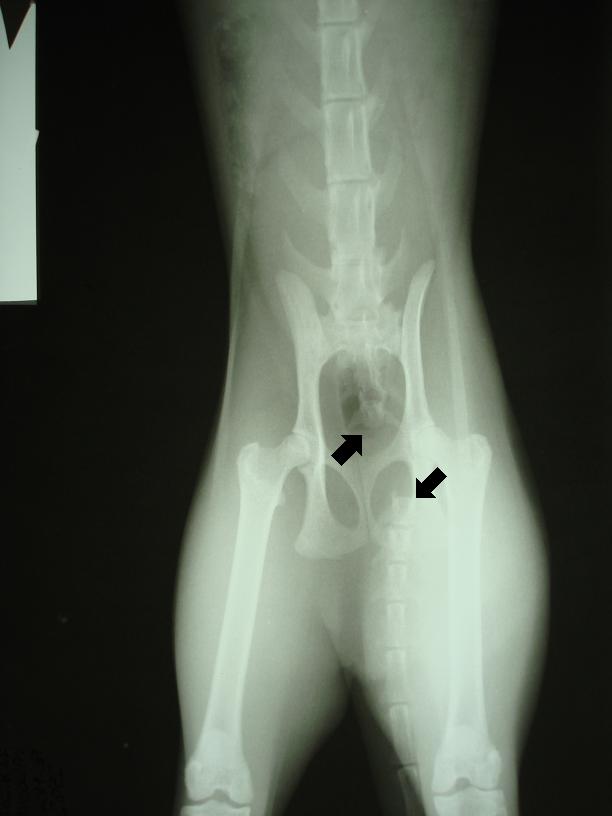

Na následujících snímcích je vidět zásadní oddálení (dislokace) 1. a 2. ocasního obratle (šipky). Došlo tedy k „odtržení“ ocasu, respektive ocasních obratlů počínaje 2. ocasním obratlem od zbylé části páteře.

Kosti pánve, zadních končetin, křížové kosti a bederních obratlů jsou rentgenologicky neporušené.